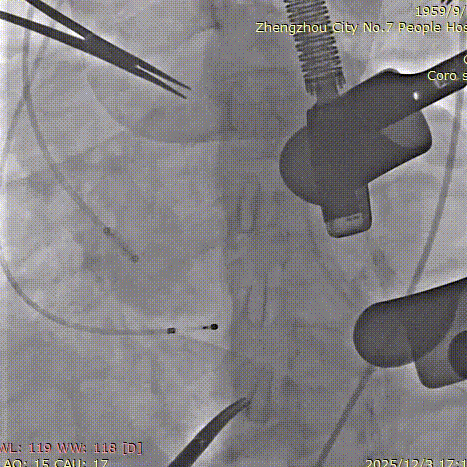

造影确认定位件入窦底

释放瓣膜

在心室中关闭外鞘、撤出输送系统

最后一枪造影,基本无瓣周漏

患者主动脉瓣重度反流纠正,术后无反流、无瓣周漏。术后心脏彩超显示人工生物瓣启闭良好,平均跨瓣压差3mmHg,流速正常。患者恢复情况良好,心功能较术前有了明显改善。